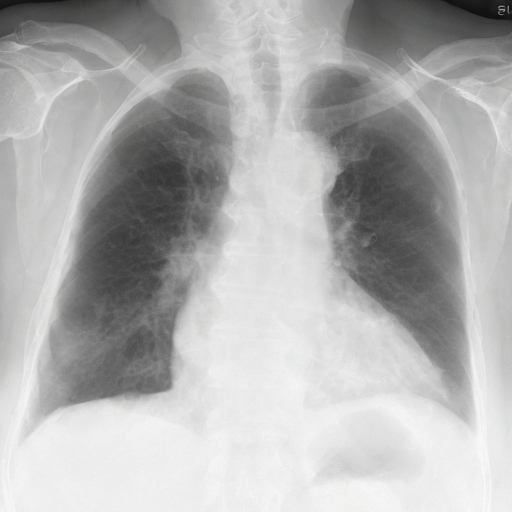

Let's load an example image of a patient with influenza.

import requests

from PIL import Image, ImageDraw

from torchvision import transforms

def download_sample_image() -> Image.Image:

"""Download chest X-ray with CC license."""

base_url = "https://upload.wikimedia.org/wikipedia/commons"

image_url = f"{base_url}/2/20/Chest_X-ray_in_influenza_and_Haemophilus_influenzae.jpg"

headers = {"User-Agent": "RadEdit"}

response = requests.get(image_url, headers=headers, stream=True)

return Image.open(response.raw)

image = download_sample_image()

input_image = transforms.Compose([transforms.Resize(512), transforms.CenterCrop(512)])(image)

right_lung_coords = [(19, 445), (53, 299), (88, 170), (128, 105), (176, 72), (205, 68), (228, 88), (233, 155), (223, 249), (178, 313), (170, 366), (172, 390), (55, 407)]

left_lung_coords = [(477, 435), (466, 298), (457, 192), (437, 132), (384, 77), (343, 65), (315, 67), (306, 102), (308, 131), (330, 140), (341, 166), (331, 192), (321, 197), (334, 252), (350, 277), (383, 305), (410, 333), (435, 368), (450, 409)]

# Create a blank image with the same size as the original image

lung_mask = Image.new("L", (512, 512), 0)

# Draw the filled shape using the coordinates

draw = ImageDraw.Draw(lung_mask)

draw.polygon(right_lung_coords, fill=255)

draw.polygon(left_lung_coords, fill=255)

For this example, we will remove the visual appearance of influence from the lungs, while preventing changes from happening to the rest of the image. To do this, we create a mask of the lung regions and use this as the edit_mask which defines the region we wish the editing prompt to be applied to. Since we want the rest of the image to remain unchanged, we use the inverse as the keep_mask which defines the region where edits are discouraged from taking place.